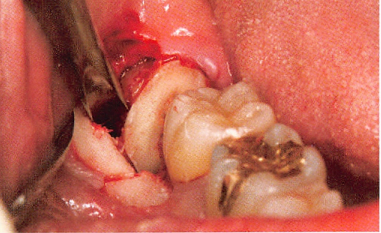

正常情况下拔牙术后疼痛适的通常3-7天消失,3个月左右拔牙窝内会长出新的骨质形成骨性愈合。而在双膦酸盐的药物影响下,牙槽骨的改建受到干扰,无法正常的完成破骨-新骨形成的过程,从而导致拔牙创经久不愈并继发感染,最终演变为颌骨骨坏死,甚至有使用过双膦酸盐药物的患者,在没有进行拔牙手术的情况下,仍然因为牙齿的发炎诱发颌骨骨坏死,这都给病人造成长期的痛苦及严重心理的负担。

临床分为3期:Ⅰ期有死骨出现但无明显临床症状;Ⅱ期病变局限在牙槽骨内,死骨暴露,并有红肿疼痛等感染症状,伴或不伴口内瘘管;Ⅲ期病变超出牙槽骨范围出现死骨,伴疼痛、感染,并至少伴有病理性骨折、口外瘘管、下颌骨下缘或鼻窦底部骨质溶解破坏3 项之一。

根据此标准,BONJ 的诊断并不困难。目前,BONJ 的发生机制尚不清楚,有人认为可能与BP 药物抑制破骨细胞功能、诱导凋亡、微血管栓塞、创伤和感染等因素有关。结合相关文献,BONJ 静脉和口服药物的发病率分别约为1%和0. 002%。目前,BONJ 尚缺乏理想的治疗方法,临床上主要使用刮除死骨、冲洗创面,高压氧等方法治疗。但是疗效并不确切,有相当大比例的患者病情迁延不愈,因此BONJ 重在预防。